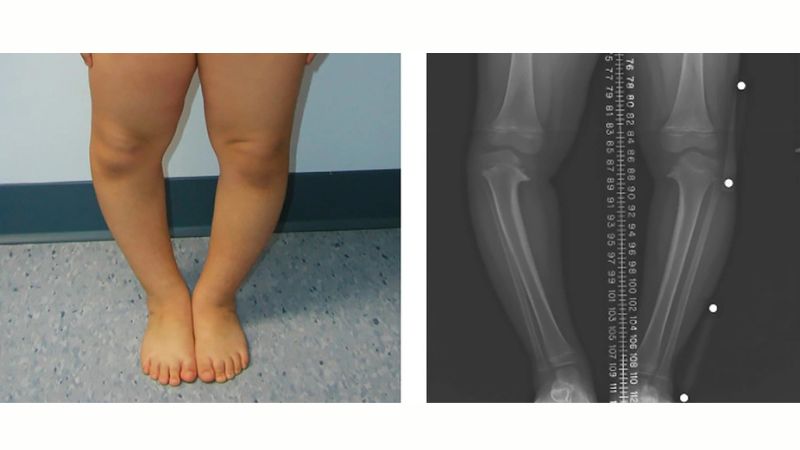

Bệnh Blount là rối loạn tăng trưởng xương hiếm gặp, chủ yếu ảnh hưởng đến trẻ em và thanh thiếu niên. Bệnh khiến phần xương chày (xương ống chân) gần đầu gối bị cong vào trong tạo nên biến dạng chân vòng kiềng (bowlegged) rõ rệt.

Nguyên nhân là do sụn tăng trưởng ở mặt trong đầu gối phát triển chậm lại hoặc ngừng hẳn, trong khi phần sụn bên ngoài vẫn phát triển bình thường. Sự phát triển mất cân đối này khiến xương bị cong ra ngoài theo thời gian, làm thay đổi trục chân và ảnh hưởng đến khả năng vận động nếu không được điều trị sớm.

Hiện tượng biến dạng xương này thường gặp ở trẻ sơ sinh đến khoảng 3 tuổi. Ở giai đoạn đầu đời, chân vòng kiềng nhẹ là hiện tượng bình thường, đặc biệt là thời kỳ trước 2 tuổi. Tuy nhiên, ở trẻ mắc hội chứng Blount, tình trạng chân bị cong không tự cải thiện mà ngày càng nặng hơn theo thời gian. Bệnh điển hình bởi các dấu hiệu dưới đây:

- Ảnh hưởng cả hai chân (song phương).

- Biến dạng chủ yếu ở xương chày – phần xương dưới đầu gối.

- Khi trẻ lớn dần, trục chân cong rõ, dáng đi lệch, dễ té ngã hoặc đau khớp gối.

Như đã đề cập đến ở trên, triệu chứng đặc trưng nhất của bệnh lý này là tình trạng chân bị cong vào trong rõ rệt ở dưới đầu gối (gọi là genu varum). Các dấu hiệu cảnh báo bệnh khác bao gồm:

- Một hoặc hai chân cong hình chữ C.

Bác sĩ sẽ khám lâm sàng để kiểm tra dáng đi, mức độ cong của chân và sự cân đối của hai bên. Ngoài ra, bác sĩ thường chỉ định chụp X-quang toàn bộ chân (từ hông đến mắt cá) để hỗ trợ:

- Quan sát độ cong và trục xương.

- Kiểm tra tình trạng sụn tăng trưởng ở đầu gối.

- Phân biệt với các nguyên nhân khác gây chân vòng kiềng.

Chẩn đoán thường được xác nhận sau 2 tuổi vì ở giai đoạn này, hiện tượng chân cong sinh lý đã tự biến mất. Nếu sau 2 tuổi mà chân trẻ vẫn cong hoặc nặng dần, bác sĩ có thể nghi ngờ trẻ mắc các hội chứng rối loạn xương hiếm gặp như Blount.

Bệnh nhân sẽ được chỉ định chụp X Quang để đánh giá bất thường ở xương